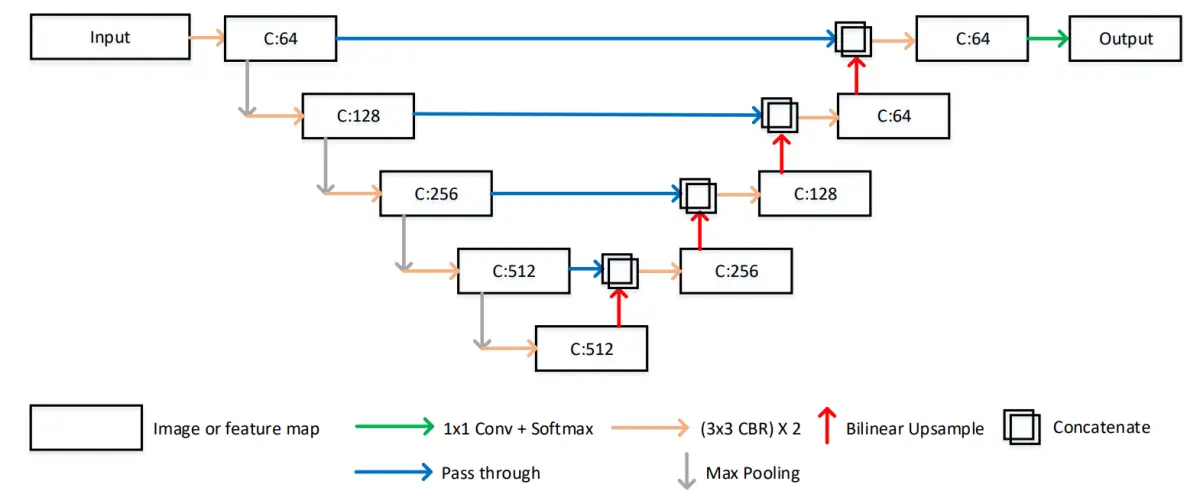

4.UNet 模型结构特点

在深度学习领域,卷积神经网络主要被用于图像上的自动特征提取,虽然目前对卷积神经网络所提取的特征还不能进行完全准确的理论解释,但目前主流思想认为:在卷积神经网络的浅层,其提取的特征主要是语义信息较低级的特征,例如边缘、颜色、亮度等,而在卷积神经网络的深层,其提取的特征主要是由低级语义特征组合得到的高级语义特征,例如形状、纹理、深度等,但由于需要更大的特征感受野以及在计算量和显存上的限制,深层特征一般都经过多次池化操作,其分辨率较低。

卷积神经网络一开始被用于图像分类领域,输入到卷积神经网络的图像在不断进行卷积和池化的过程中,提取到的特征逐渐积累聚合成为高级的语义特征,最终获取到关于整幅图像的唯一语义特征向量,并将该特征向量用于图像的分类工作,但在图像分割领域,最终要求输出每个像素点的分类信息,因此设计模型结构时,需要在最终的输出上保持特征图的分辨率和输入图像接近,同时还要求高分辨率的特征具备较高级的语义信息以提高分割效果。

在RonnebergerO等人的工作中针对上述问题设计了独特的特征提取结构:UNet模型,该模型被提出之后在后续的代码实现上有一些改进,略微不同于原论文的描述,但目前对UNet的具体实现一般如图所示,其中C表示对应特征图的通道个数,Conv表示卷积层,CBR表示卷积层、Batch Normalization操作以及ReLU激活函数的组合,Conv和CBR前面的3x3或者1×1均表示其中卷积层的卷积核大小。

总体来说,UNet模型主要包括U型的编解码结构以及中间的横向连接结构,这种结构包含了两种特征传递路径,第一个路径是将深层的特征逐层上采样,第二个路径是将浅层的特征逐层和上采样的深层特征进行融合,这种结构设计最终可以输出高分辨率的特征图,并且该特征图上的每个像素特征都包含高分辨率的低级语义信息以及低分辨率的高级语义信息,这种特征对于语义边界较为模糊的分割任务有较大的帮助,另外相对于其他分割模型,UNet模型的结构简单,参数量较少,且由于横向连接的存在,训练过程中不容易出现梯度消失的情况,收敛速度更快,因此对标注数据数量的要求不高。在医学图像分割领域,一般存在语义边界较为模糊、标注数据量较少两个问题,UNet对于这两种问题都有较好的缓解,因此UNet 结构成为了目前深度学习医学图像分割领域的最常见模型结构。

8.改进的MA-Unet结构

参考该博客给出的改进方案,MA-Unet分为两个部分,分别为编码器与解码器。由于U-Net在跳跃连接时存在无效的语义信息,故在编码器中每一层的特征图在经过卷积层之后加入CBAM。在CBAM的通道注意力模块中,通过通道注意力机制来加强特征,抑制其他无效特征,从而提高网络精度;在CBAM的空间注意力模块中,空间注意力机制可从已进行上采样的特征图中恢复空间信息。针对U-Net对尺度信息提取不足的问题,在编码器最后一层通道数为1024的特征图后加入改进的ASPP模块。通过ASPP模块可以实现对不同尺度特征的提取,在低层阶段获得精细的目标像素分割定位,在高层阶段提取更为有效的特征,从而提高分割精度。在解码器中,为了解决图像存在的不同尺寸的物体的多尺度问题,对每一个尺度的特征图进行串联,在最后进行提取时,特征图包含了各个尺度的信息特征。通过跨尺度信息聚合的方式可以解决“同物异谱,异物同谱”的问题。